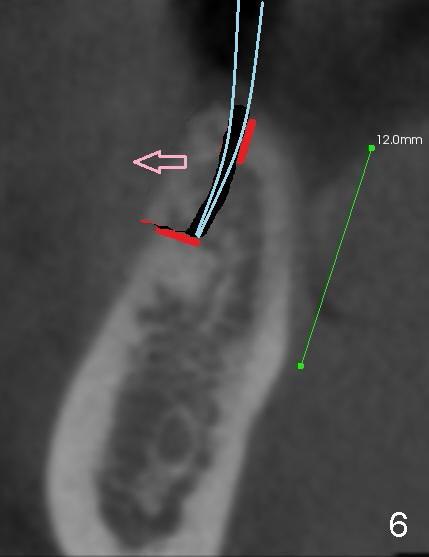

The patient is scheduled to return for implant placement 3 weeks later. The red lines in Fig.4 (CT coronal section) represent bony cuts in the ridge. A transverse incision is made over the top of the ridge with minimal exposure of the ridge. A curved osteotome is inserted into the upper bony cut (Fig.5). As the chisel is tapped in, the buccal segment moves buccally (Fig.6 pink arrow). When the chisel is withdrawn, a pilot drill is used to initiate osteotomy (Fig.7). As drills increase in diameter, the buccal segment continues moving buccally (Fig.8). Finally a bone-level implant (4.1 or 4.5x12 mm, Fig.9) or sub-crestal implant (4 or 4.5x8) is placed. Will the ridge split work?